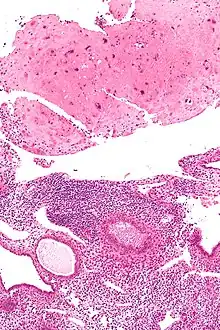

| Micrograph of a placental site nodule (top of image). H&E stain. |

Typically, they consist of pink (hyaline) material using the standard stain and contain few cells. Bizarre multinucleated cells may be present; however, there is no mitotic activity. The differential diagnosis includes (cervical) squamous cell carcinoma, gestational trophoblastic disease, and exaggerated placental site.